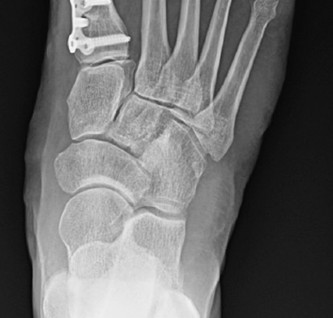

Proximal Metatarsal Osteotomies (e.g., Opening/Closing Wedge): Used for severe deformities or when significant IMA correction is needed.

- Often require plate and screw fixation or staples.

-

Key Consideration: After the osteotomy and translation, ensure the first MTP joint is stable and congruent. The goal is to achieve an HVA of 5-10° and an IMA of <9-10°.

Medial Capsular Plication and Closure

- Medial Capsular Plication: The medial capsular flap, previously preserved, is imbricated or plicated to tighten the medial capsule and help maintain the corrected alignment of the hallux. This reinforces the medial structures and prevents recurrence.

- Caution: Over-tightening the medial capsule is a common cause of postoperative hallux varus. The repair should be snug but allow for full, unrestricted range of motion of the MTP joint without placing the hallux in a varus position. Test the range of motion and alignment through the full arc of motion.

- Skin Closure: Close the subcutaneous layers and skin with absorbable and non-absorbable sutures, respectively.

Dressing: Apply a sterile dressing, often with a soft compression bandage or a specialized bunion dressing (e.g., a "bunionette dressing" or "figure-of-eight" bandage) that supports the corrected position without overcorrection.

Figure 6: Postoperative radiograph demonstrating appropriate alignment after hallux valgus correction, including medial eminence resection and osteotomy, with stable fixation.